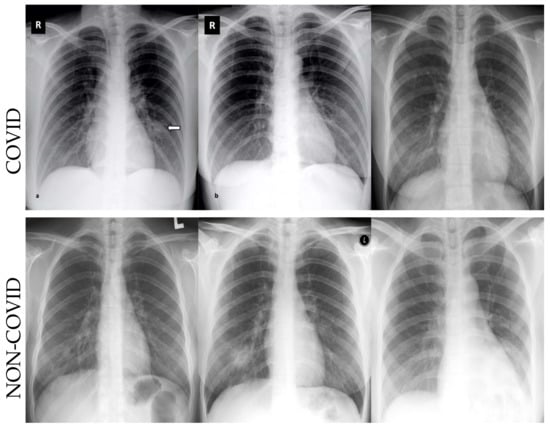

- We employ the deep learning algorithms for COVID-19 datasets to detect infection in the CT and X-ray images;

4.2. Datasets